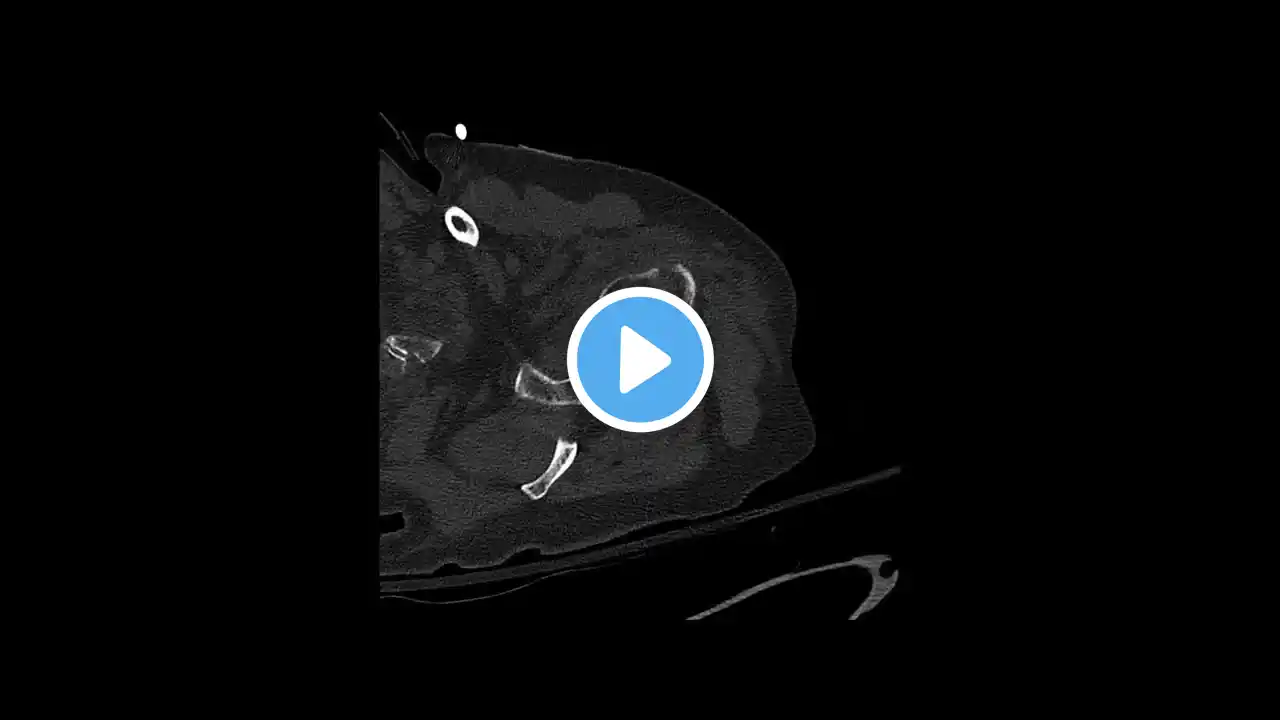

Chest CT: Subtle Right Anterior Sternoclavicular (SC) Dislocation

This is a 60-something female with an atraumatic right sternoclavicular (SC) joint dislocation or subluxation. This was an incidental and very subtle finding on a chest CT obtained for cancer screening. She has no pain and responded well to conservative management. SC Dislocation https://wikism.org/Sternoclavicular_J... SportsMedReview: Shoulder Pain https://www.sportsmedreview.com/by-jo... Physical Therapy Resources https://www.sportsmedreview.com/physi...